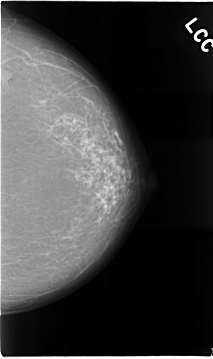

C_0016_1.LEFT_CC

LEFT_CC LINES 4664 PIXELS_PER_LINE 2768 BITS_PER_PIXEL 12 RESOLUTION 50 NON_OVERLAY

FILE: C_0016_1.RIGHT_CC.OVERLAY

TOTAL_ABNORMALITIES 1

ABNORMALITY 1

LESION_TYPE MASS SHAPE IRREGULAR MARGINS SPICULATED

ASSESSMENT 5

SUBTLETY 5

PATHOLOGY MALIGNANT

TOTAL_OUTLINES 1